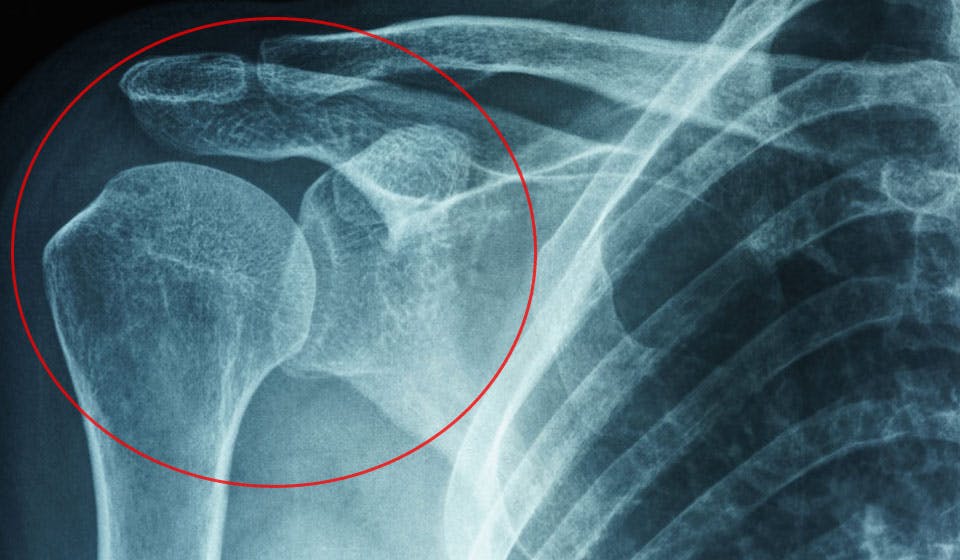

FRUSEN AXEL Överarmsbenet är fäst vid skulderbladet med en led som hålls på plats av en bindvävsfylld kapsel. Vid en frusen axel uppstår det en form av inflammation i ledkapseln. Det gör bindväven stel och samtidigt blir det en vävnadspåbyggnad och produktionen av smörjande ledvätska hämmas. Det ger dig sämre rörelseförmåga och orsakar smärtor.

Axeln är extremt viktig för rörligheten i din arm. Så när axeln plötsligt fryser fast är du i riktig knipa. Överarmsbenet är fäst vid skulderbladet med en led som hålls på plats av en bindvävsfylld kapsel. Vid en frusen axel uppstår det en form av inflammation i ledkapseln. Det gör bindväven stel och samtidigt blir det en vävnadspåbyggnad och produktionen av smörjande ledvätska hämmas. Det ger dig sämre rörelseförmåga och orsakar smärtor.